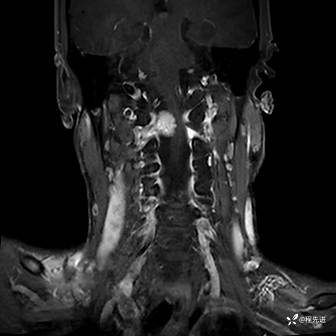

MRI平扫+增强:

T1增强: